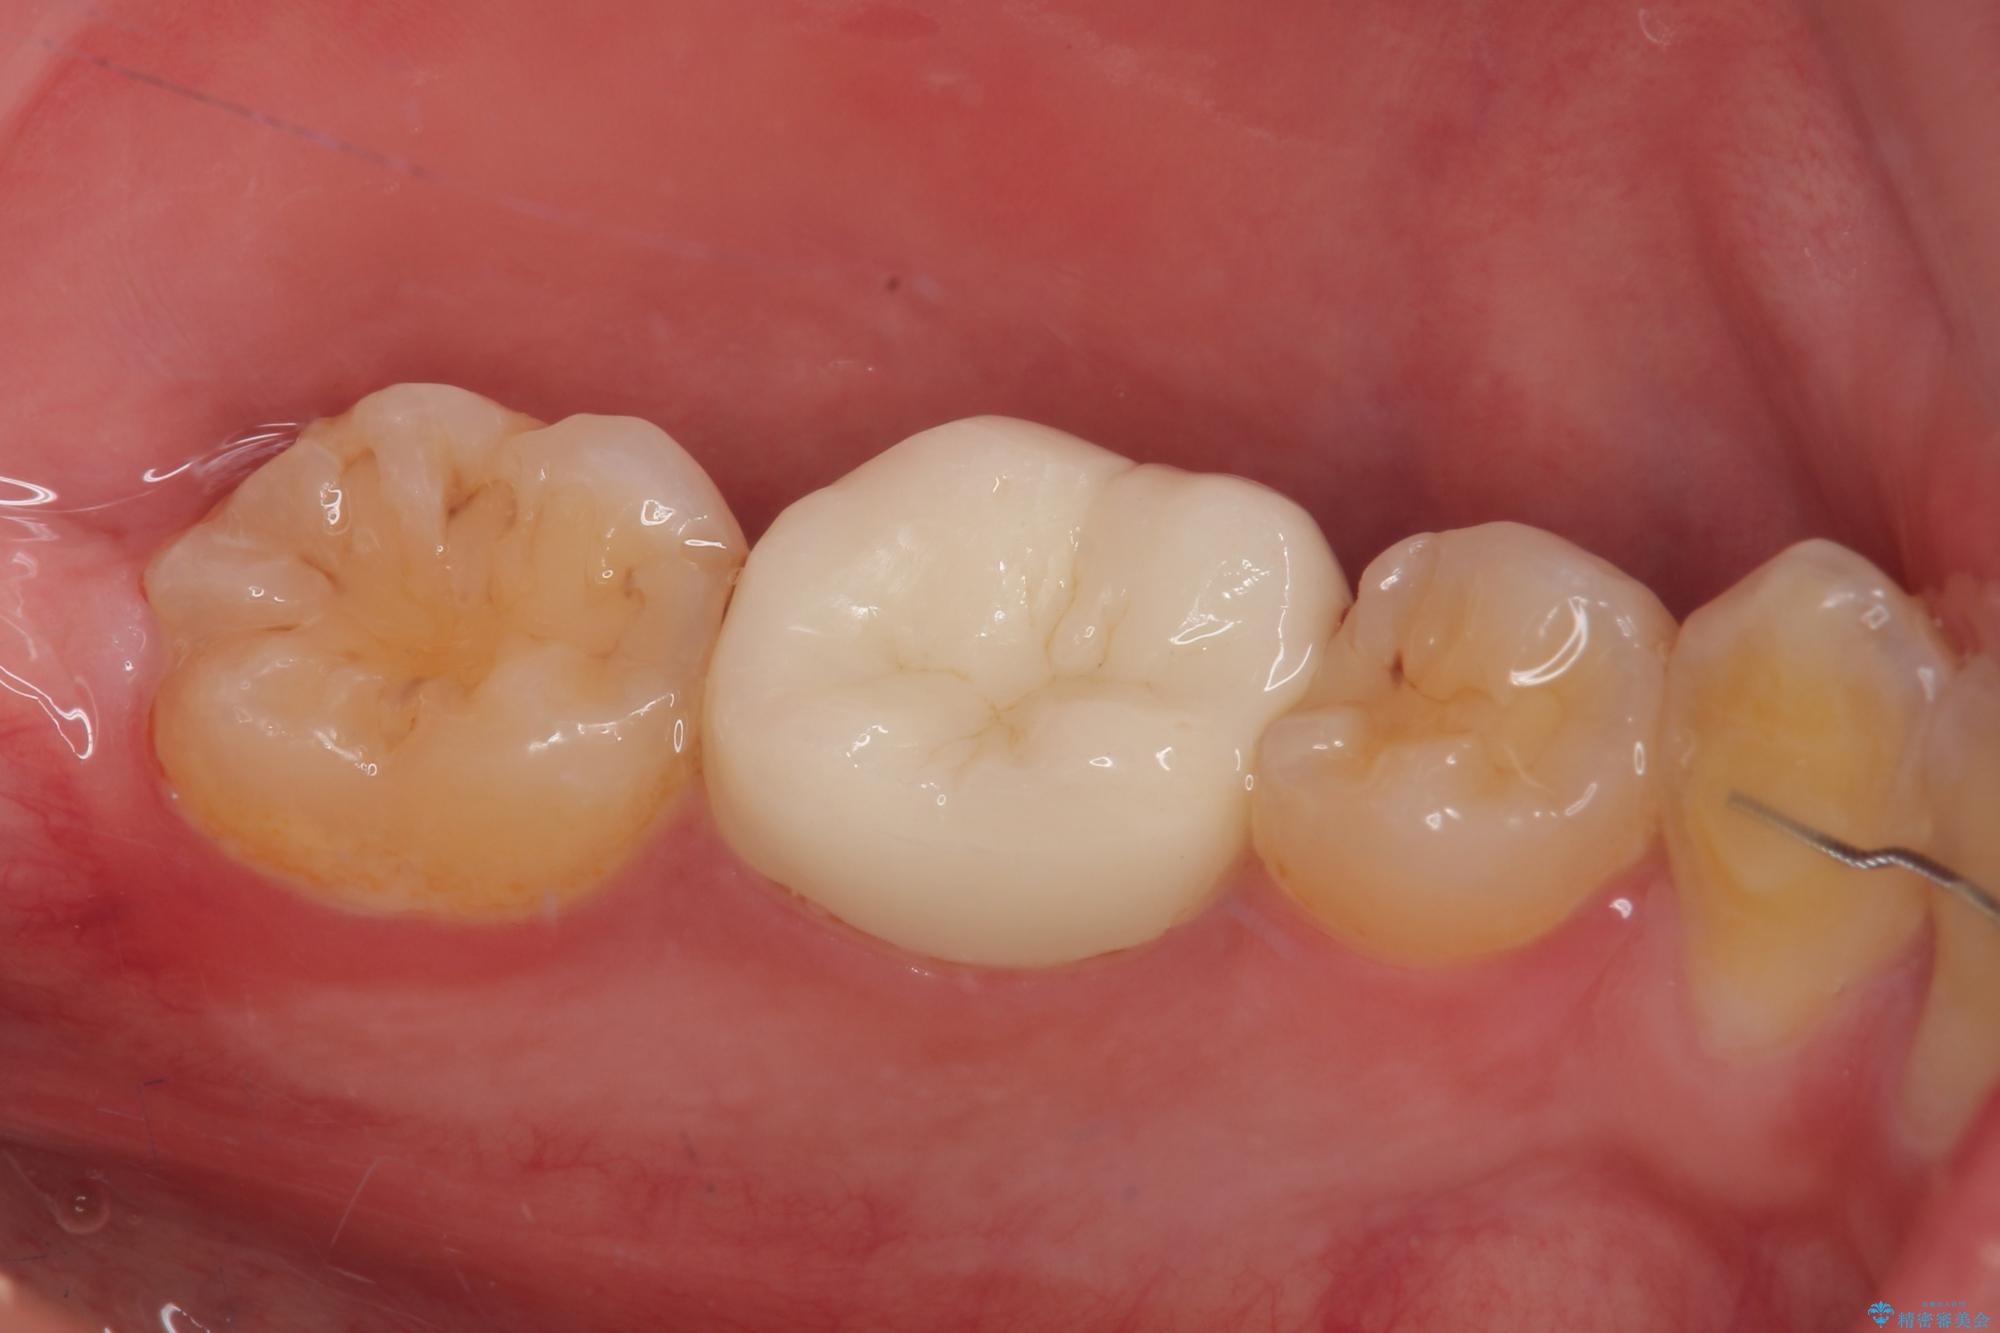

歯と歯茎の間に圧排糸と言われる糸を入れてシリコーン印象材にて精密な型どりをしました。

虫歯による不快な症状がなくなり喜んでいただきました。セラミックの被せものが入った後の違和感なく過ごせているそうです。矯正治療終了直後の被せもの治療なのでリテーナーの作成回数をできるだけ少なく迅速に行うことを考慮して治療を行いました。

今後、ホワイトニングを行う予定なので、患者様のご希望により、周りの歯に比べてあえて白い被せものを作成しました。